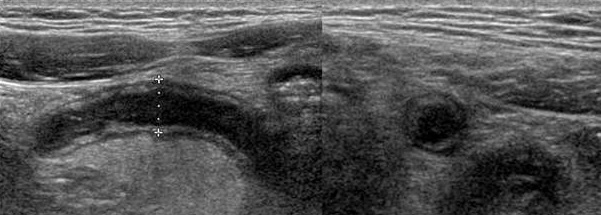

arguments pour une invagination iléo-colique

- diamètre > 2 cm et longueur > 3 cm

- ganglion ou appendice dans le boudin

- jonction iléo-colique non visualisée

invagination iléo-iléale = plutôt > 2a

- diverticule de Meckel

- lymphome, tumeur, purpura rhumatoïde